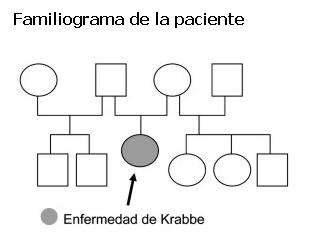

Paciente de 10 meses, sexo femenino, procedente de Rocha, primera hija de la pareja de padres no consanguíneos. Padre de 62 años de edad y madre de 28 al momento del nacimiento de la paciente. No se aprecia situación similar en la familia. En la figura 1 se muestra el familiograma. Embarazo bien controlado, parto a término, eutócico. Peso al nacer: 3.230 g, perímetro cefálico (PC): 33 cm, talla: 50 cm. Sin patología perinatal. Controlada en salud, esquema de vacunación vigente, con buen crecimiento y desarrollo hasta los 7 meses. Posteriormente, pérdida de conductas adquiridas sin nuevos logros en las diferentes áreas del desarrollo. A los 10 meses presentaba pobre seguimiento visual, sin sonrisa social, hipotonía generalizada que dificulta la sedestación y el sostén cefálico. No balbuceo ni laleo. No toma objetos. Irritabilidad excesiva. Desde los 7 meses no había habido ganancia de peso, presenta vómitos reiterados y dificultad en la alimentación.

Actualmente el objetivo del diagnóstico es para orientación familiar en base a asesoramiento genético, por tratarse de una enfermedad genética con herencia autosómica recesiva, el riesgo de recurrencia es del 25% en cada futura gestación de la misma pareja. Es importante saber que es posible el diagnóstico prenatal mediante el análisis de la actividad de la enzima galactocerebrósido-b-galactosidasa de vellosidades coriales o de cultivos de amniocitos. Para algunos autores, se debería evitar el diagnóstico prenatal basado solamente en el análisis directo de las vellosidades coriales pues la toma de la muestra conlleva el riesgo de contaminación con tejido materno que presenta niveles enzimáticos por sobre los rangos de diagnóstico (6,9). El diagnóstico prenatal también es posible realizando estudio molecular de ADN fetal, pero para ello es indispensable conocer las dos mutaciones en el caso índice o afectado de la familia previo al diagnóstico prenatal (5).